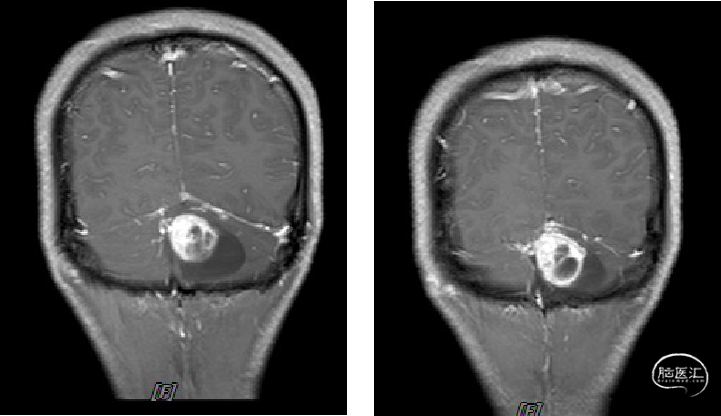

术前MRI

image.png

诊断及手术方式

术前诊断:

1.小脑、延髓占位(血管母细胞瘤)

2.梗阻性脑积水